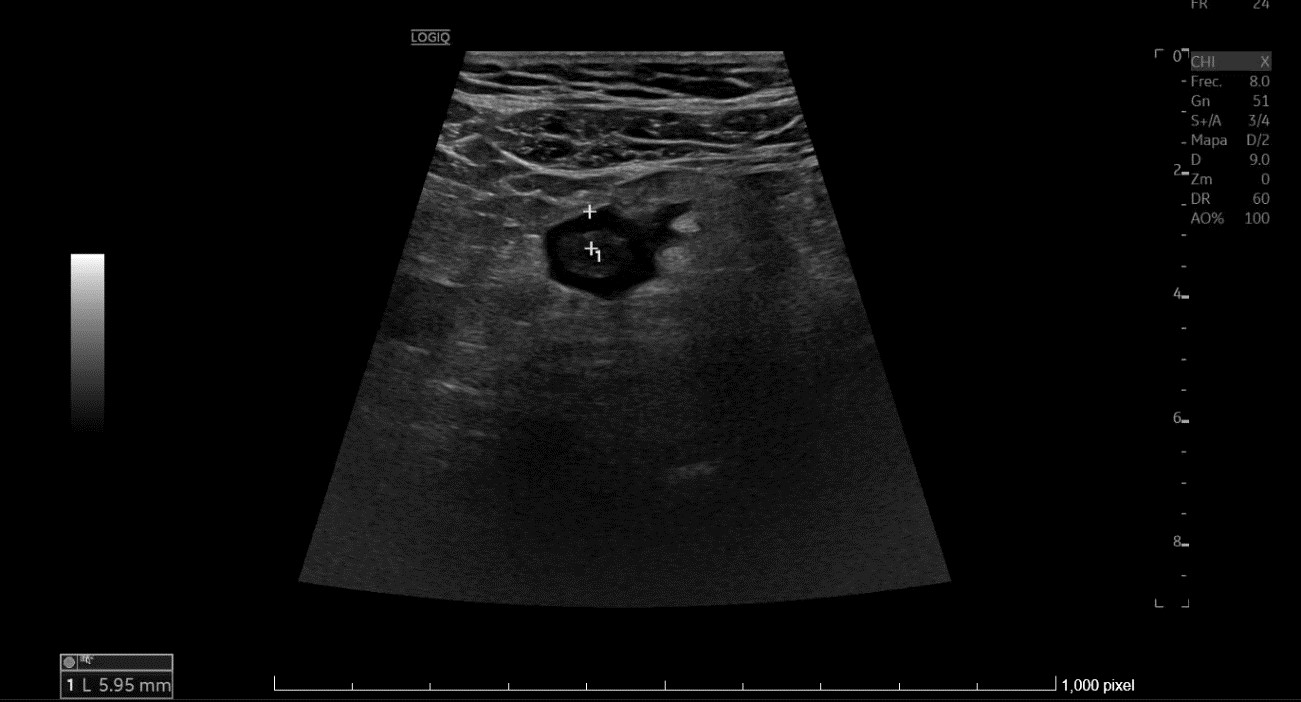

• En urgencias, de inicio se realiza radiografía abdominal sin datos de obstrucción intestinal. Ante persistencia de dolor intenso, leucocitosis y aumento de PCR en analítica, se repite la ecografía (utilizando también sonda lineal) con hallazgo de diverticulitis aguda sigmoidea con datos de peritonitis regional pélvica, y posteriormente se realiza un TC abdominal con conclusión de diverticulitis aguda con pequeños abscesos murales, perforación de un divertículo y peritonitis pélvica.